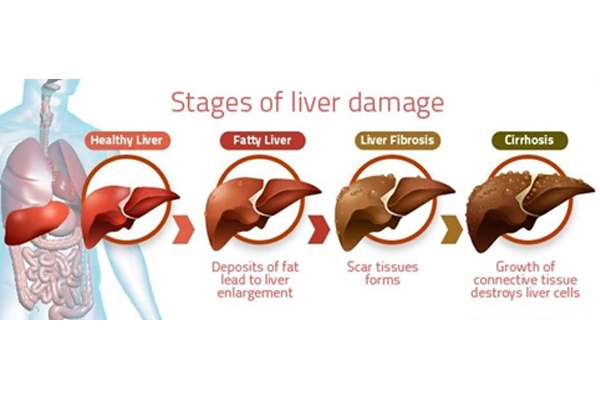

Non-Alcoholic Fatty Liver Disease is increasingly common worldwide and linked to obesity, diabetes, and metabolic syndrome. Recent research underscores that MASLD treatment centers on lifestyle modification and drug therapies targeted at metabolic risk factors.